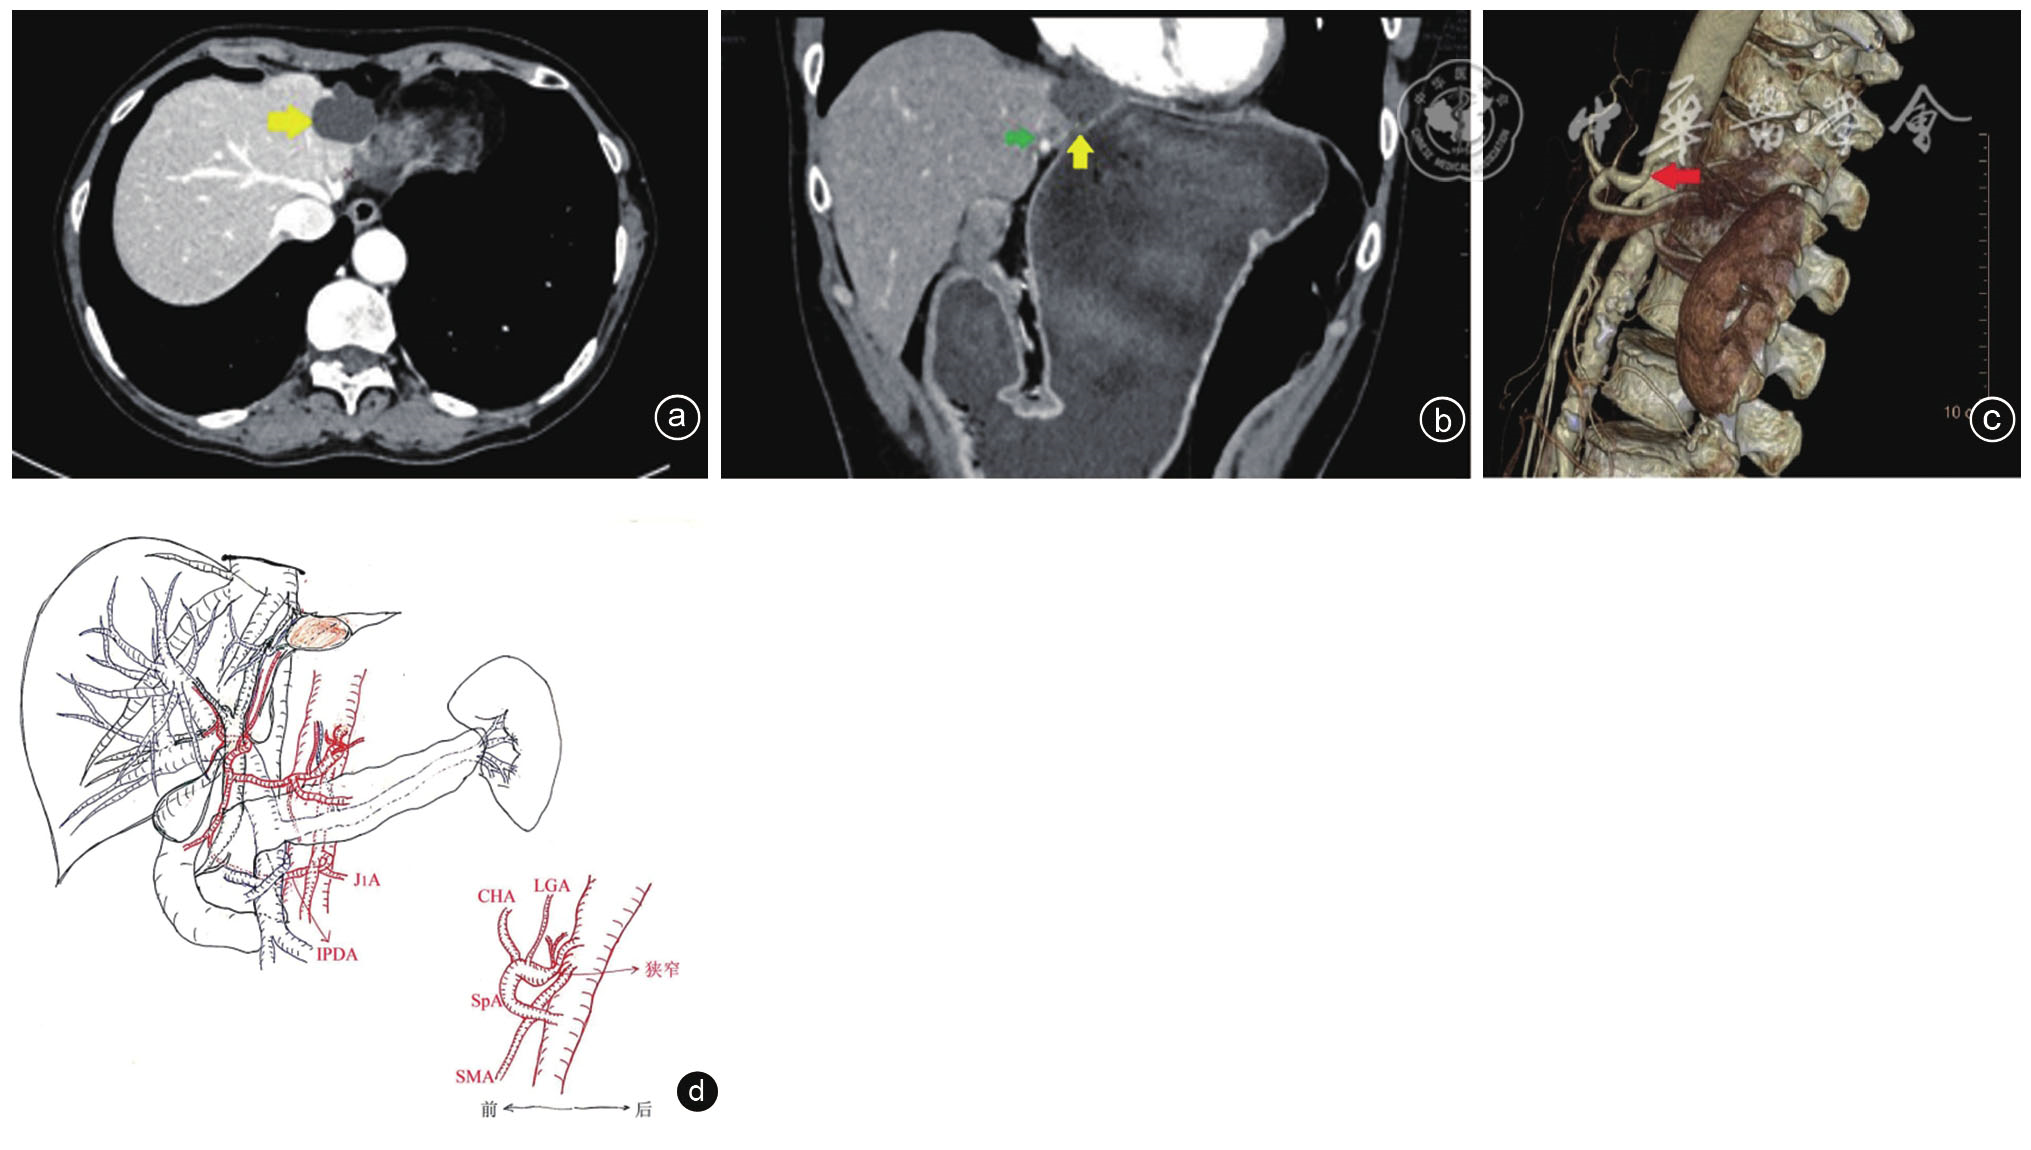

图1 以图文形式总结正中弓状韧带综合征合并左半肝萎缩、囊性占位患者病例特点 注:a、b分别示萎缩的左半肝和囊性占位(黄色箭头)的横断位和冠状位CT图像(绿色箭头示肝左动脉及扩张的左外叶胆管);c示腹腔干CT血管造影的三维重建图;d示病例的手绘图[描绘:(1)腹腔干起始部前上方明显的Ⅴ型凹陷外压改变(红色箭头),狭窄远端扩张,呈典型钩状形态;(2)明显萎缩的左半肝和囊性占位];J1A为第一空肠动脉;IPDA为胰十二指肠下后动脉;CHA为肝总动脉;LGA为胃左动脉;SpA为脾动脉;SMA为肠系膜上动脉